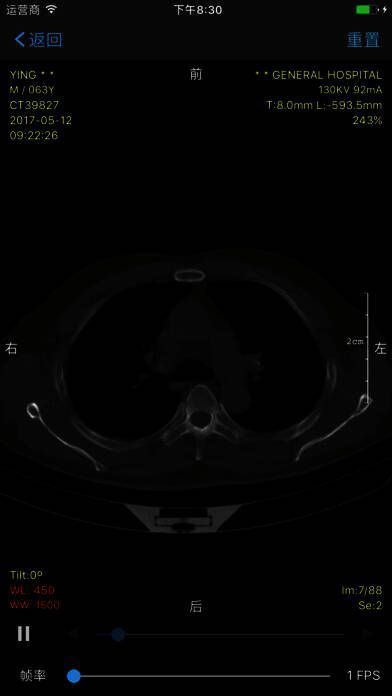

1. 原始数据,高清影像:采用 DICOM 格式,完整保存信息细节,精度更高。

4. 秒传秒开,顺滑流畅:运用领先的 GPU 计算、影像预加载、影像本地保存等技术,杜绝卡顿、模糊和长时间加载等待。

- 原始数据,高清影像:DICOM 格式,信息细节全保存,精度更高。

- 秒传秒开,顺滑流畅:领先的 GPU 计算、影像预加载、影像本地保存等技术,拒绝卡顿、模糊、加载等待时间过长。